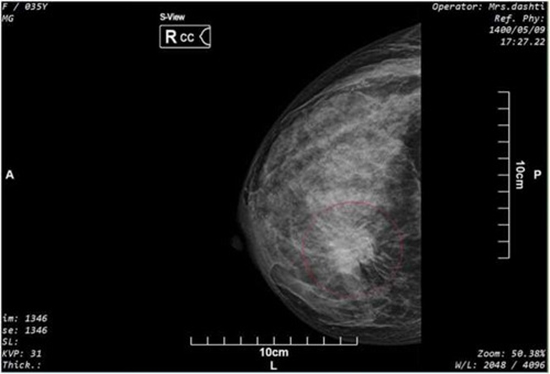

Background: Synthesized Mammogram (SM) from Digital Breast Tomosynthesis (DBT) images is introduced to replace the routine Full Field Digital Mammography (FFDM) to reduce radiation dose.

Purpose: to compare the conspicuity of cancer related findings between SM and FFDM and combination of these methods with DBT.

Methods: The study was conducted in a tertiary breast imaging center, where 200 women referred for screening were enrolled in the study sequentially. Patients underwent FFDM and DBT simultaneously and a two-year follow-up was done. Data was evaluated for Breast Imaging Reporting and Data System (BI-RADS) score, breast density, mass lesions, calcification, and focal asymmetry by two expert breast radiologists. Comparison between different methods was made by Cohen Kappa test.

Results: 22 patients with likely malignant findings went under biopsy. Taking histopathologic findings and two-year follow up as reference, the overall sensitivity and specificity for FFDM+DBT (86.1 and 88.9 respectively) and SM+DBT (86.1 and 88.2) didn't show a meaningful difference. Comparing SM and FFDM, calcification in 20 subjects were overlooked on SM, but later detected when combined with DBT. Considering breast composition and BI-RADS categorization, an excellent agreement existed between the readers.

Conclusion: Screening with SM+DBT shows comparable results with FFDM+DBT considering BI-RADS categorization of the patients. Although SM showed slightly inferior sensitivity compared to FFDM, after combining DBT with SM no malignant appearing calcification or mass lesion was missed.